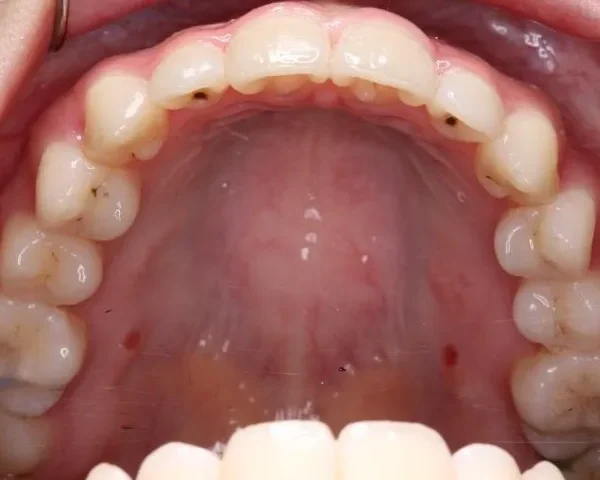

初診時年齢 高校生 (女性) 主訴 歯並びがガタガタ・口元の突出感

診断名 叢生・開咬・上下顎前突 装置名

特徴 ゆがんで生えている

状態 ガタガタ・でこぼこに生えている(叢生)

前歯で噛めない(開咬/オープンバイト)

ガタガタの歯並びにお悩みの患者様でした。

口唇の突出感の他、下顎面高が長い印象も認められました。